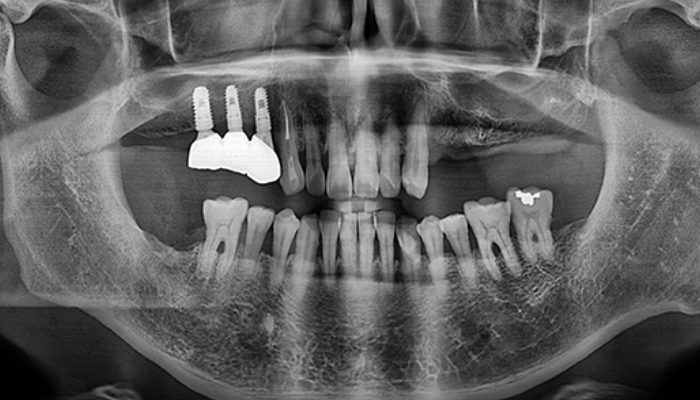

임플란트 수술시, 상악동과 잇몸뼈 사이에 뼈가 남아 있지 않았을 때 상악동막을 들어올리고 빈 공간에 뼈를 이식하여 임플란트 식립을 위한 공간을 확보하는 수술을 상악동 거상술이라 합니다.

밀도가 높고 두꺼운 턱뼈가 구성된 아래턱과는 달리 위턱은 얇은 뼈 위에 코와 광대 사이 빈 공간에 식립해야 하는 고난도 수술로 임플란트 수술 경험이 많은 의료진에게 받는 것이 중요합니다.

치아를 빼고 오래 방치하거나 치아를 잡고 있는 치조골이 많이 녹은상태에서 치아를 빼면 위쪽 턱뼈가 부족할 수 있습니다.